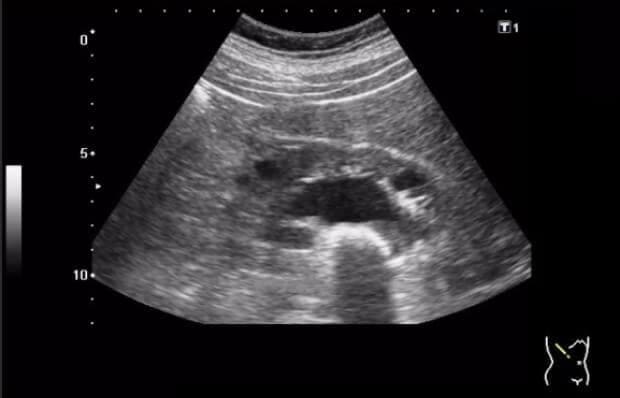

Еден месец подоцна, ултразвукот покажа дека цистата е двојно помала – од 20 mm на 10 mm! A два од трите камења се растворија и ги исфрлив од телото (се сеќавам на болката при мокрење неколку дена пред тоа). Потоа се вратив на редовната доза. Еден месец подоцна, докторот беше шокиран кога направивме ултразвук – бубрезите ми беа чисти!